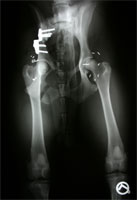

HD vor DBO Operation

Abbildung 2 a: Idealkandidat nach enggefasster Indikationsstellung präoperativ

HD nach DBO Operation

Abbildung 2 b: Der selbe Patient nach DBO. Die Spuren einer erfolglosen Goldakupunktur-Therapie sind zu erkennen.